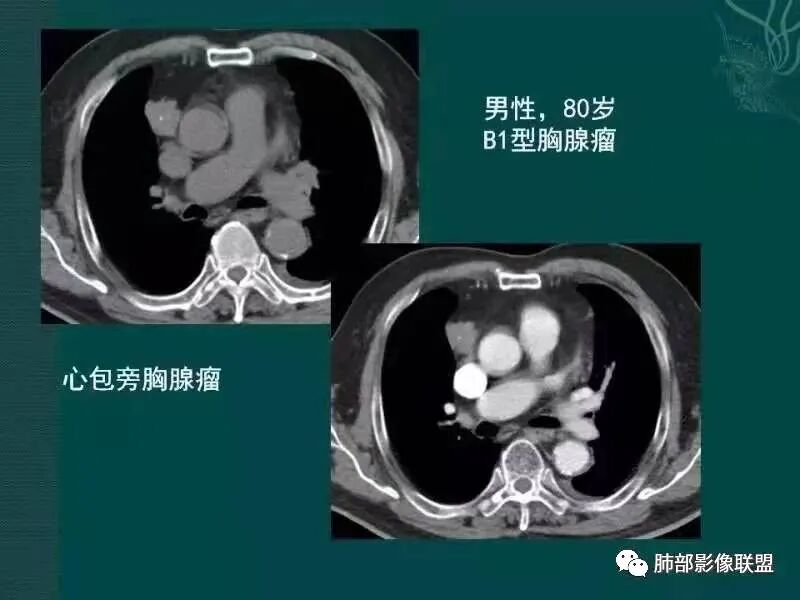

黄勇老师胸腺瘤总结

【每日晨读】胸腺瘤or胸腺癌,且听南边老师娓娓道来

胸腺瘤之罕见类型